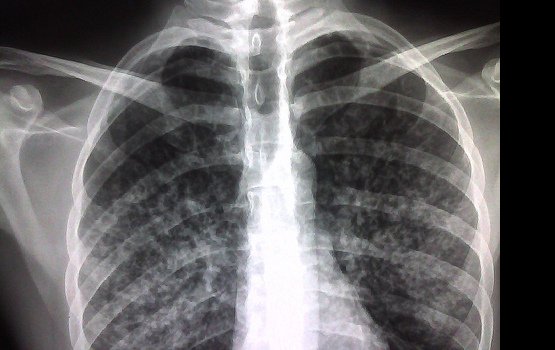

Латвийский инфектологический центр заявил: с одной стороны, заболеваемость туберкулезом за последние годы в республике снизилась вдвое, а с другой – наблюдается рост этого опасного заболевания среди детей в возрасте до 14 лет.

Главный врач Туберкулезно-легочной клиники центра Андра Цируле сообщила: Латвия по-прежнему находится в зоне высокого туберкулезного риска, и вопрос пора решать на национальном уровне.

Всемирная организация здравоохранения (ВОЗ) включила Эстонию, Латвию, Литву и Болгарию в список 27 стран мира с высокой степенью резистентного туберкулеза. Из стран – членов Евросоюза в этот перечень вошли только вышеназванные страны.

Как отмечает председатель правления Латвийского туберкулезного фонда Янис Лейманис, медицинское обследование на туберкулез и его лечение для пациентов осуществляется бесплатно. Однако бесплатность лечения не гарантирует ожидаемого эффекта. И это пугает. Общее число больных в 2011 году составило 788 человек, умерли от болезни 12 человек. Только за два первых месяца текущего года зафиксировано 138 первичных случаев заболевания, из них в 16 случаях туберкулезом заболели дети, а в двух – подростки.

Настораживает решение некоторых родителей не вакцинировать своих детей против туберкулеза, что, по мнению советника по вопросам туберкулеза Европейского регионального бюро ВОЗ Ричарда Залескиса, является преступлением. Со слов эксперта, по заболеваемости туберкулезом страна занимает третье место в Евросоюзе, регистрируется 35 смертей на 100 тыс. населения. Тогда как в Западной Европе этот показатель ниже более чем в шесть раз. «Если родители в Латвии сейчас отказываются от вакцинации детей против туберкулеза, то это преступление, потому что непривитый ребенок может умереть», – предостерегает Залескис. Доктор Ивета Озере, продолжая эту мысль, замечает: в последние годы охват детей вакцинацией против туберкулеза снизился до 95%.

Туберкулез принято признавать социальным заболеванием, однако даже самые успешные и чистоплотные от него не застрахованы. Поэтому всем, независимо от условий проживания и достатка, следует помнить о своевременном прохождении медицинского осмотра, в том числе рентгена легких.